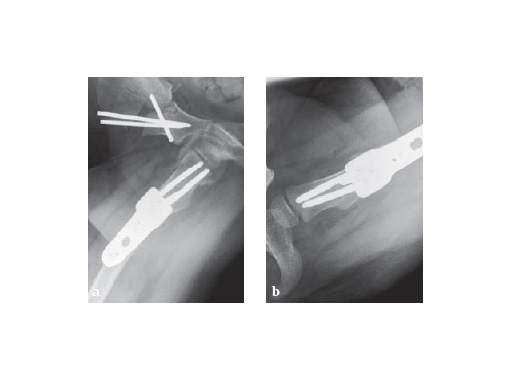

Postoperative x-ray with planned correction

Fig. 1-2